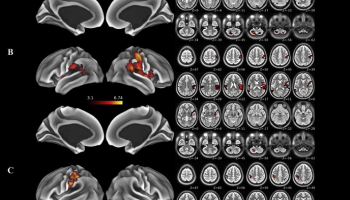

سبق وأجريت دراسات على حيوانات التجارب استهدفت رسم خريطة عصبية للدماغ، ولكن الدراسة الحالية الأولى التي وثقت النتيجة لدى الأشخاص